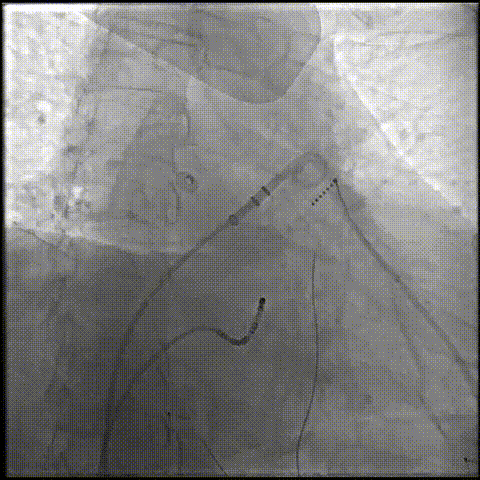

锚定伞锚定在主干区域,再将封堵盘逐渐打开,保证封堵效果,封堵盘完全打开后造影,外盘覆盖外口,封堵完全,无残余分流。

打开封堵盘

打开封堵盘造影